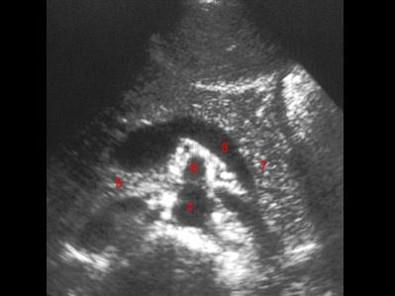

图示3所指部位?(?)A.脾静脉B.腹主动脉C.肠系膜上动脉D.胰头E.左肾静脉

问题 图示3所指部位?(?)

选项 A.脾静脉 B.腹主动脉 C.肠系膜上动脉 D.胰头 E.左肾静脉

答案 A